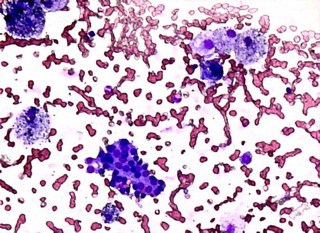

Základní vyšetřovací metodou při podezření na karcinom je pečlivé palpační vyšetření štítné žlázy a krku a ultrazvuk této oblasti, včetně vyšetření krčních lymfatických uzlin. Ultrazvuk je metoda široce dostupná, a proto by každý hmatný uzel ve štítné žláze měl být ultrazvukem vyšetřen. Ultrazvuk také rozhodne, zda stačí uzel zkontrolovat s časovým odstupem nebo zda je nutné provést punkci uzlu pod ultrazvukovou kontrolou (tzv. FNAB – fine needle aspiration biopsy).

FNAB je jednoduché vyšetření, jehož bolestivost je srovnatelná s běžným odběrem krve. Provádí se po lokální desinfekci krku dvěma vpichy tenkou jehlou do uzlu pod ultrazvukovou kontrolou. Tím je získán materiál na cytologické vyšetření (vyšetření shluků buněk pod mikroskopem). Je-li výsledek FNAB pozitivní nebo podezřelý, je nutná operace (odstranění jednoho nebo obou laloků štítné žlázy). V případě negativního nálezu lze s velmi vysokou pravděpodobností (více než 95 %) zhoubný nádor vyloučit. I v těchto případech však má být velikost uzlu pravidelně kontrolována ultrazvukem a při zvětšování či jiného podezření z malignity je indikována kontrolní FNAB či operace. Pokud uzel roste nebo je jakkoliv jinak podezřelý, musí být provedena operace, i když je FNAB negativní. FNAB nikdy nemá 100 % diagnostickou výtěžnost a průměrně v 5-10 % je třeba odběr opakovat. Je-li odběr opakovaně nediagnostický, je indikována operace.